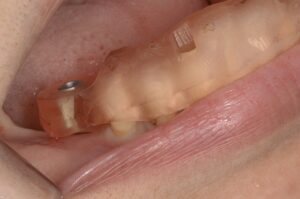

今回のインプラントは下顎臼歯部の欠損を主訴に来られた患者さんです。上顎にもむし歯があります。

今回もコンピュータガイドを使って1本1本埋入位置を確認していきます。インプラントを埋める本数やデザインは最も好ましい条件から最低限の条件まで提示し、患者さんと相談の上進めていきます。今回は3本のインプラントを埋入しました。

ガイドを作成し、適切な位置に埋入します